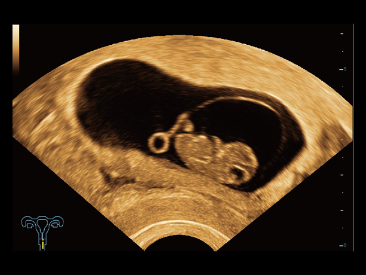

Oltre alla qualit├Ā delle immagini di livello eccellente, Resona 7 migliora anche le capacit├Ā di ricerca clinica il rivoluzionario V Flow per la valutazione emodinamica vascolare, e l'acquisizione piani pi├╣ intelligente dal set di dati 3D per la diagnosi del sistema nervoso centrale fetale. Combinando il pi├╣ intuitivo funzionamento multi-touch basato su gesti e tutte le caratteristiche cliniche essenziali, Resona 7 sta veramente portando nuove tendenze nellŌĆÖinnovazione dellŌĆÖecografia.